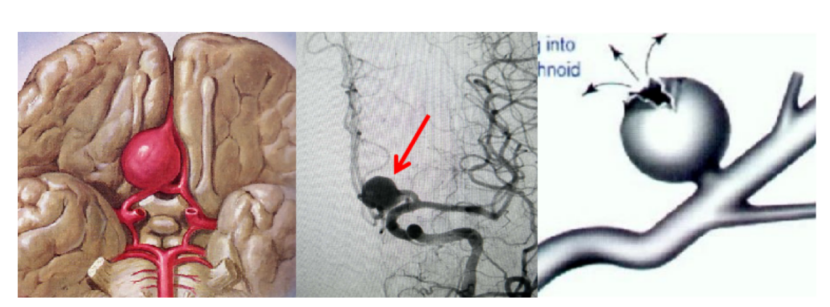

脑卒中是人类健康的“第一杀手”,2018年全球疾病负担报告显示,中国人群总体卒中风险高达39.3%,每12 秒就有1位脑卒中新发患者,每21 秒就有1人死于脑卒中,脑卒中已成为我国第一大致残和致死疾病。

急性缺血性脑卒中(acute ischemic stroke,AIS)又称脑梗,作为最常见的脑卒中类型,约占我国脑卒中的69.6%~70.8%,一年病死率高达14.4%~15.4%,致残率达33.4%~33.8%,给无数家庭带来了沉重的负担和痛苦,神经介入血管内治疗是AIS治疗方式之一。